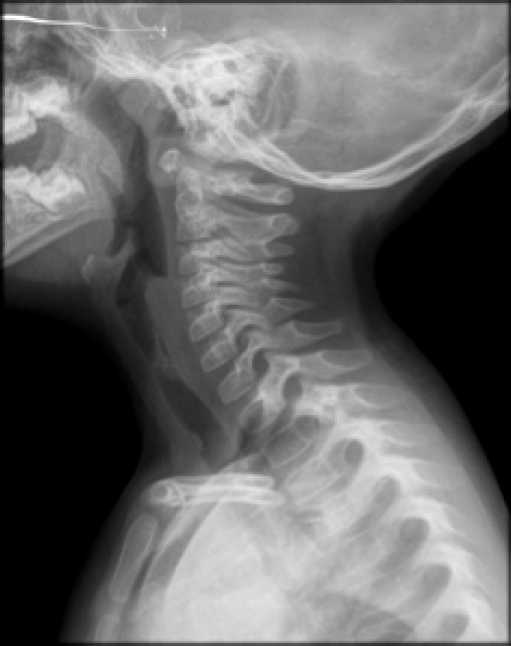

Chest and neck radiographs were requested for an initial approach (Figure 1 and 2). The radiology service found a steeple sign that suggested laryngeal croup in the anteroposterior (AP) projection of the second image. Likewise, the lateral projection shows an object that could be a foreign body. Chest X-ray was normal.

Lateral x-ray projection of the neck.

Figure 2: Lateral x-ray projection of the neck.

Source: Own elaboration based on the data obtained in the study.